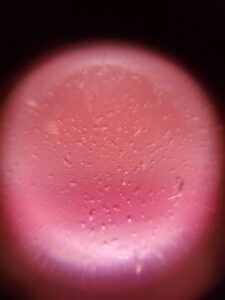

petitIBIS-D13-2